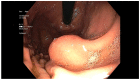

Gastric and esophageal tumors are diverse neoplasms that involve mucosal and submucosal tissue layers and include squamous cell carcinomas, adenocarcinomas, spindle cell neoplasms, neuroendocrine tumors, marginal B cell lymphomas, along with less common tumors. The worldwide burden of esophageal and gastric malignancies is significant, with esophageal and gastric cancer representing the ninth and fifth most common cancers, respectively. The approach to diagnosis and staging of these lesions is multimodal and includes a combination of gastrointestinal endoscopy, endoscopic ultrasound, and cross-sectional imaging. Likewise, therapy is multidisciplinary and combines therapeutic endoscopy, surgery, radiotherapy, and systemic chemotherapeutic tools. Future directions for diagnosis of esophageal and gastric malignancies are evolving rapidly and will involve advances in endoscopic and endosonographic techniques including tethered capsules, optical coherence tomography, along with targeted cytologic and serological analyses.